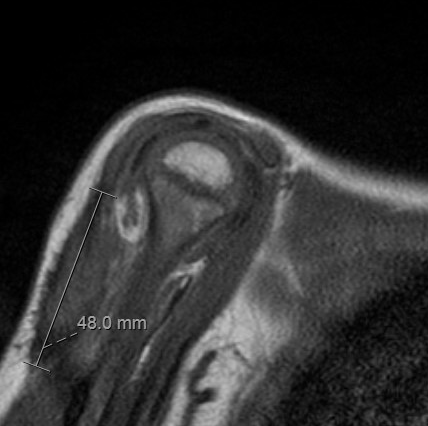

• • The work-up for Infantile Fibromatosis often consists of a physical examination, X-ray, MRI, CT, and bone scans. The diagnosis is often confirmed with a biopsy, which samples the tumor for further analysis. Differential diagnoses include hemangiomas, infantile fibrosarcoma, and other soft-tissue tumors.

Radiographic imaging is used to help form a diagnosis of infantile fibromatosis. These include X-Ray, MRI, CT and Bone Scans

An example of an MRI is shown.